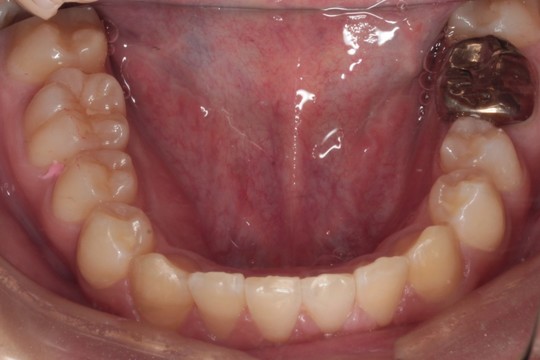

下顎 治療前

下顎 治療後

調布市の20代男性

主訴:前歯のデコボコを直したい

使用装置:インビザライン

治療期間:約2年

治療費用:93.5万円(税込)

治療結果:叢生が改善されました